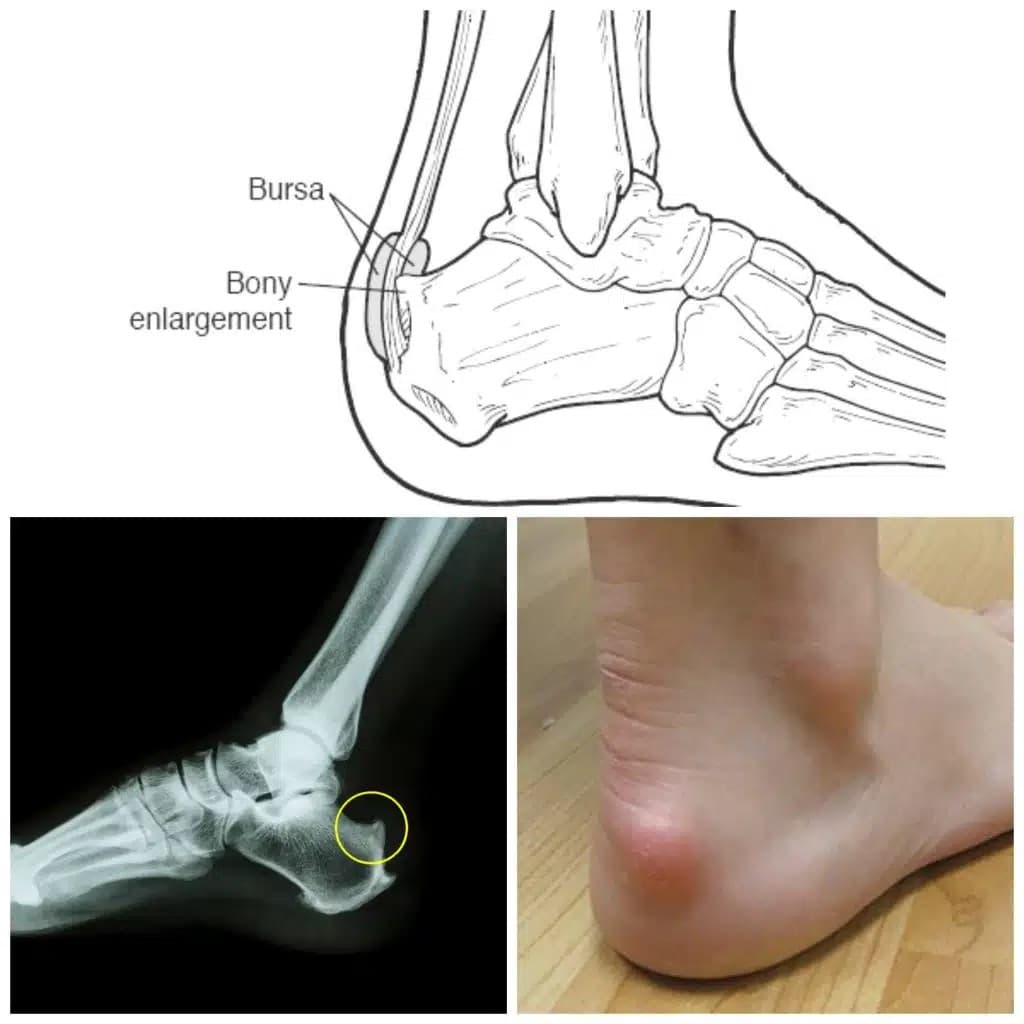

Haglund's deformity is a bony bump that forms on the back of the heel bone, right where the Achilles tendon attaches. It's often caused by pressure from rigid-backed shoes, but genetics and foot structure also play a role. The bump can irritate the bursa — a fluid-filled sac between the tendon and the bone — leading to painful inflammation known as bursitis. For over 8 years, I endured the discomfort, the flare-ups, and the frustration of a condition that made every run, every walk, and every step a negotiation with pain.